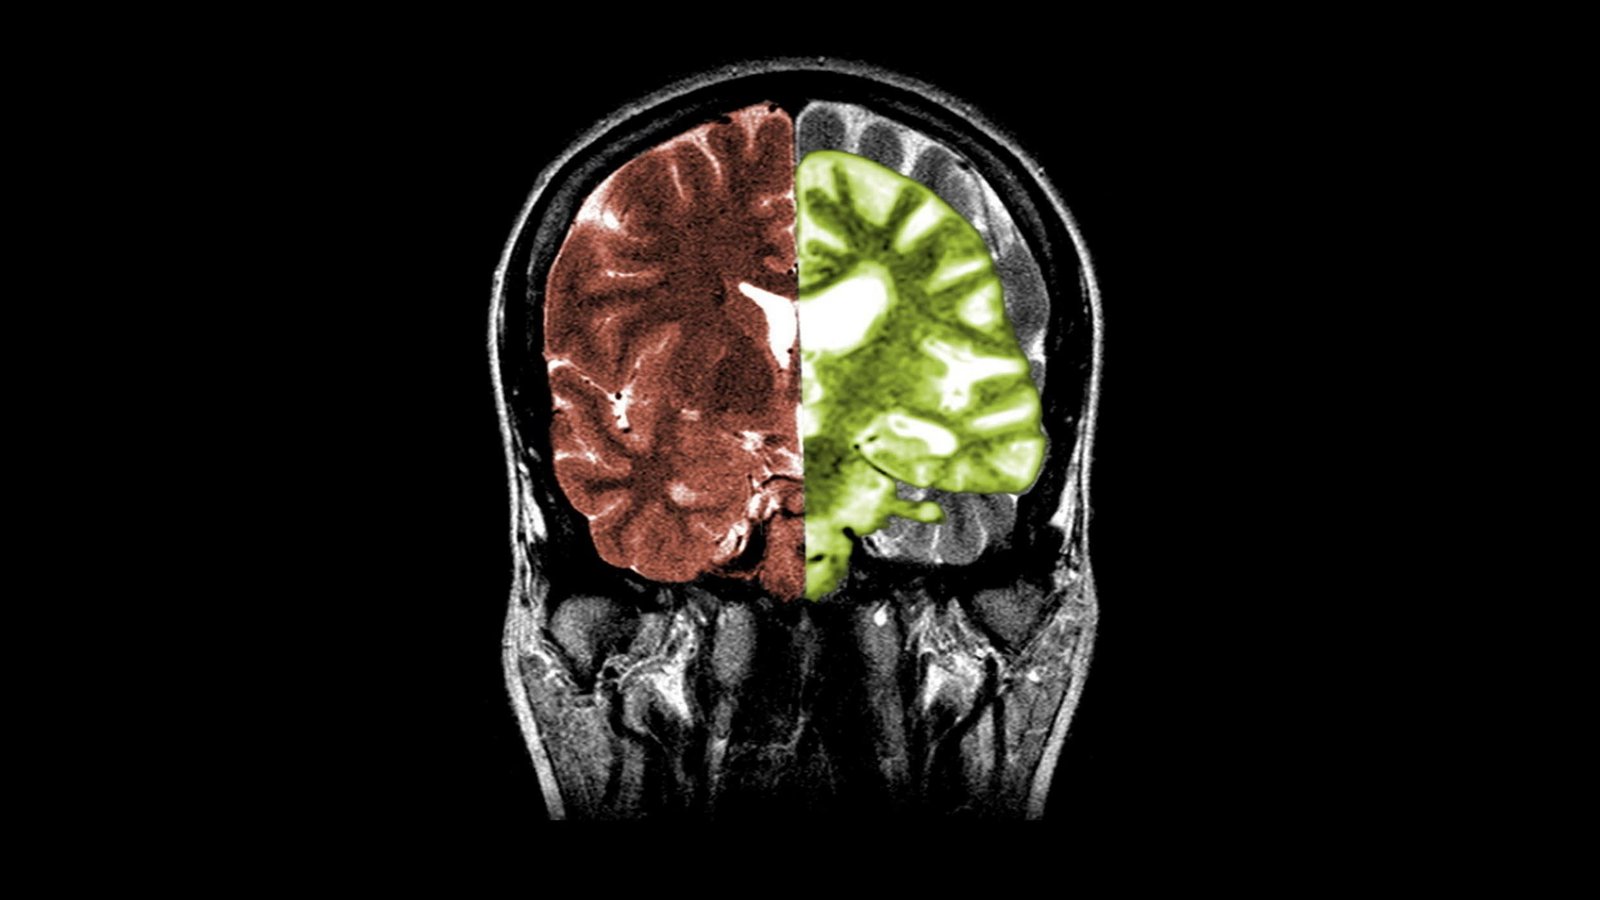

Hints to help large biological databases identify nervous diseases and fight